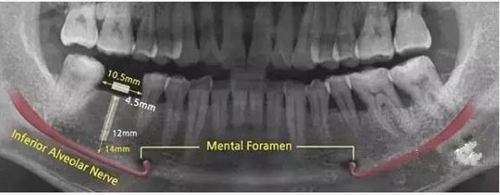

因此治療的第三階段就包括牙周手術(shù)(若需要)和缺牙修復(fù)(包括種植牙)。